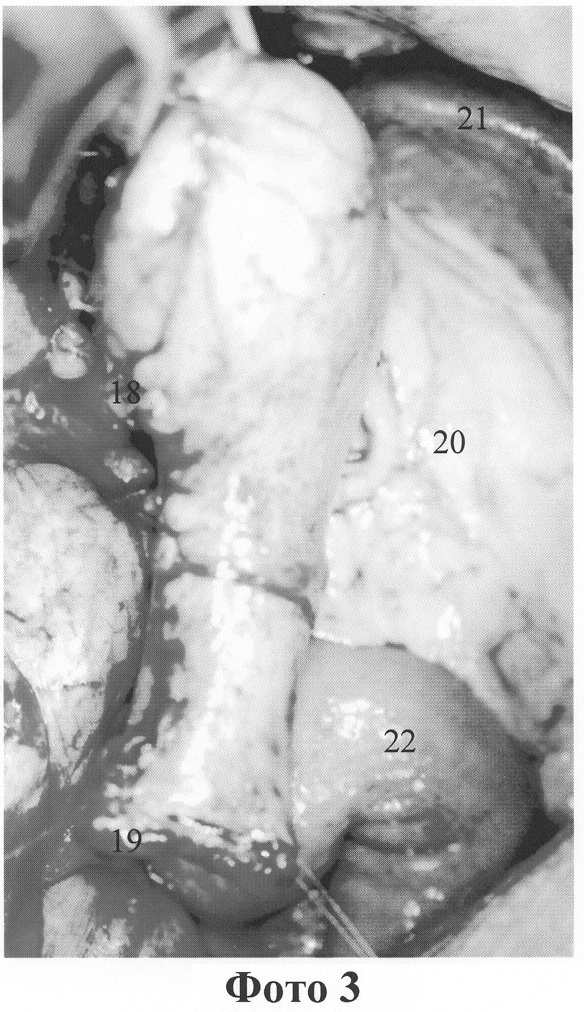

Интраоперационное исследование: В верхнем этаже брюшной полости умеренно выраженный спаечный процесс. Желудок резецирован на 2/3 по Бильрот II, анастомоз на короткой петле, без межкишечного соустья (приложение фото 1, 7 – малый сальник, 14 – ГПОД, 15 – культя желудка, 16 – область ГЭА, 17 – расширенная приводящая петля (синдром приводящей петли). В области ГЭА имеется язва, в начальном отделе отводящей петли пальпируется инфильтрат. Культя желудка большого размера, имеется аксиальная кардиальная грыжа пищеводного отверстия диафрагмы. Мобилизовано дно культи путем пересечения диафрагмально-фундальной связки с условием сохранения коротких артерий дна желудка, денервирована и деваскуляризирована вся малая кривизна культи и абдоминальный отдел пищевода на протяжении 6 см. Произведена резекция ГЭА с экономной ререзекцией культи желудка (приложение фото 3, 18 – пластическая реконструкция культи желудка, 19 – экономное удаление пептической язвы, 20 – большой сальник, 21 – селезенка, 22 – тощая кишка) и резекцией участка тощей кишки вместе с кратером пенетрирующей язвы с зоной инфильтрации (приложение фото 2, 7 – малый сальник, 2 пересеченная приводящая петля ГЭА, 18 – пластическая реконструкция культи желудка, 19 – область ГЭА, 23 – арефлюксная кардия). Восстановлена арефлюксная кардия путем создания связочного аппарата пищевода и восстановления угла Гиса. Малая кривизна культи желудка ушита однорядным серозно-мышечным швом с формированием цилиндрической трубки длиной 5 см и диаметром около 2 см. Выделена из рубцовых сращений ДПК, вскрыта, иссечен шов культи. ДПК мобилизована.